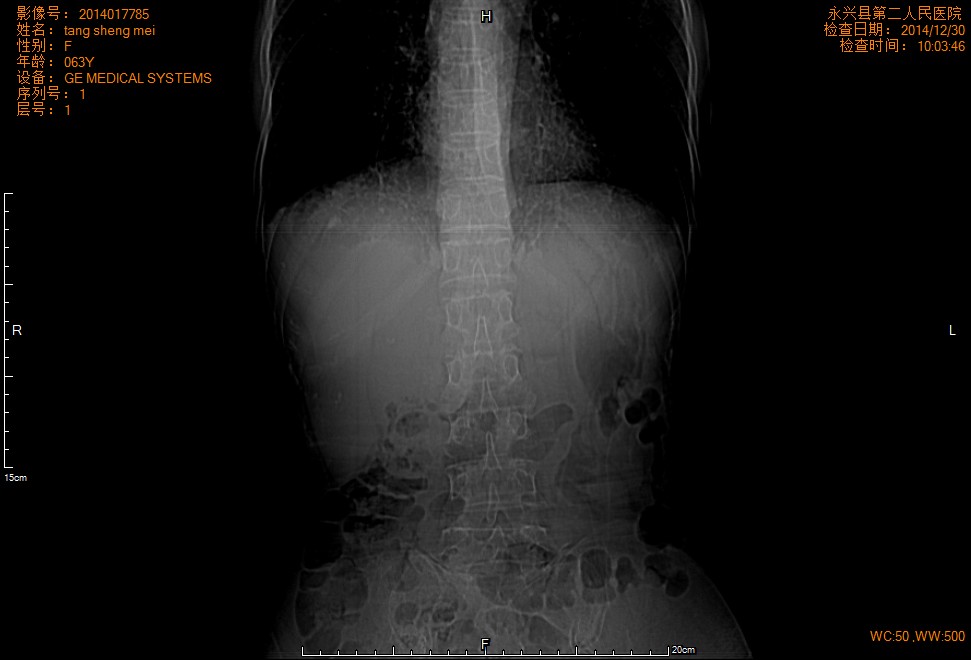

CT49659:肝内多发囊状占位

病 史;上腹部不适一个月,B超提示肝内占位,就这么简单 了.下面 的医院就这样

肝内多发转移瘤确定无疑,至于原发病灶在哪需要讨论,本人愚见有两种可能:1、胃肠道肿瘤肝内转移;2、肝内肿瘤肝内转移。

胃窦部明显增厚,呈肿块状,窦腔缩小。考虑胃癌并肝转移。

考虑多发囊性转移瘤可能

胆管细胞癌伴肝内转移

胆管细胞癌伴肝内转移.

胆管细胞癌

胃癌肝转移,胃粘液腺癌?

肝癌并肝内多发转移瘤